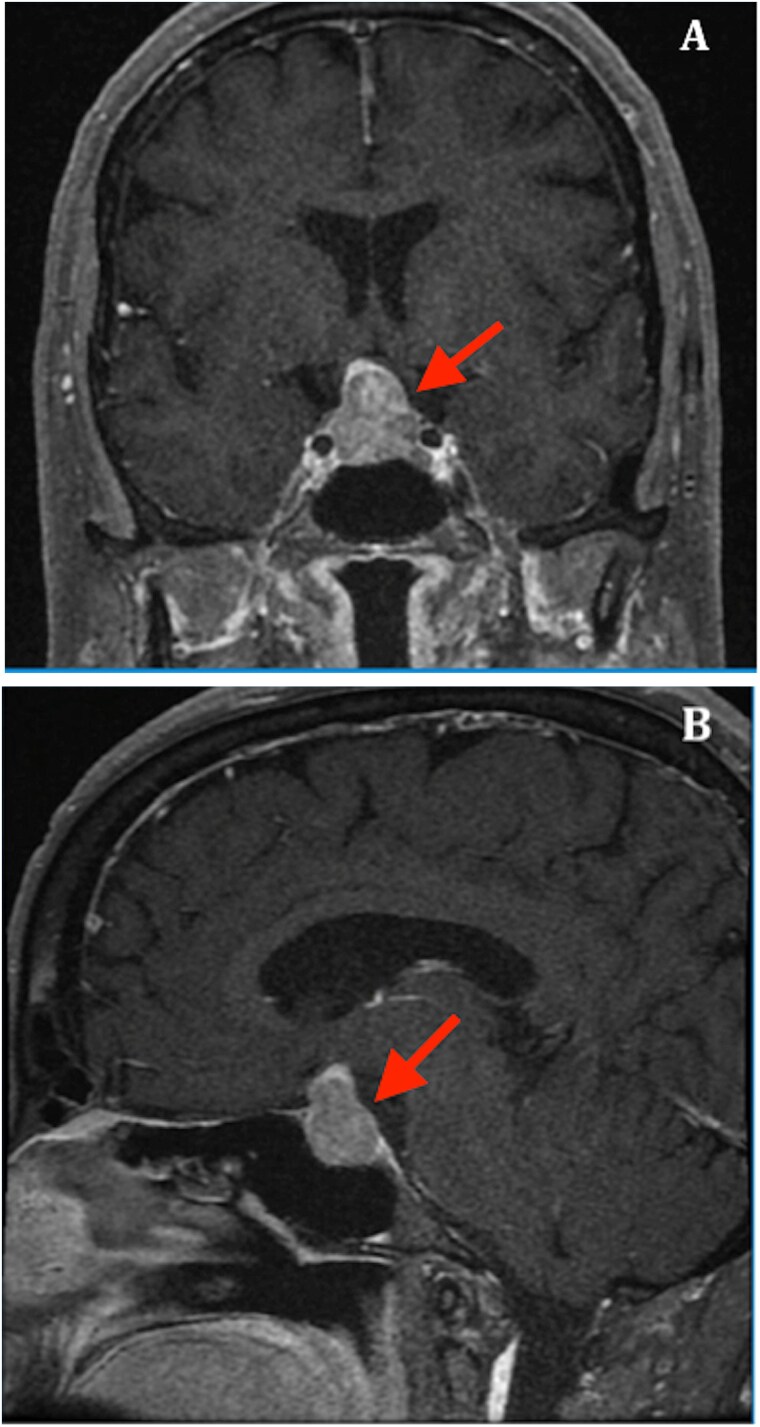

Clinical case: We describe the case of a patient with a non-functioning pituitary adenoma who underwent transsphenoidal surgery. On postoperative day 7, she developed isolated SIAD, characterized by a plasma sodium level of 113 mmol/L, normovolemia, urine osmolality of 364 mOsm/kg, and urine sodium concentration of 50 mmol/L. A daily fluid restriction of 800 mL resulted in the resolution of hyponatremia within 48 h.